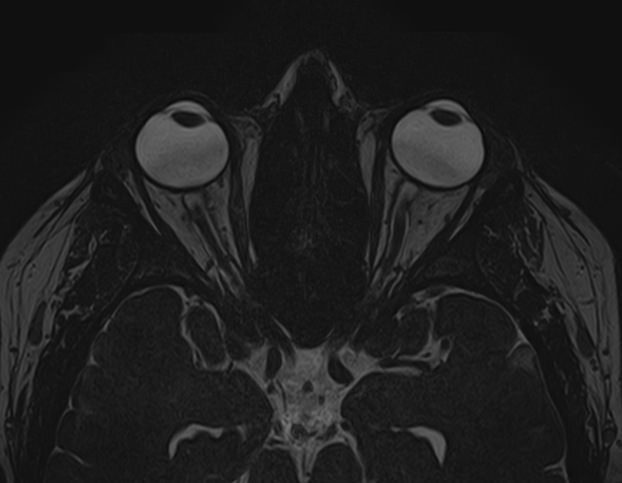

МРТ глазных орбит является современным способом диагностики патологии глазниц, в которых расположены глазные яблоки и их придатки (окружающая жировая клетчатка, зрительные нервы, слезные железы, мышцы глаза, связочный аппарат, кровеносные сосуды). МРТ орбит также позволяет получить детальную информацию о состоянии мягких тканей периорбитальных областей (тканей, окружающих глазницу).

Магнитно-резонансную томографию назначают при необходимости детального изучения мягкотканных структур глазниц. В результате исследования получают срезы анатомической области, на которых можно рассмотреть мельчайшие элементы. МРТ орбит обеспечивает визуализацию следующих структур:

• элементы глазного яблока, включая оболочки;

• периорбитальная клетчатка;

• мышечный аппарат;

• зрительный нерв;

• слезные железы.

Ангиорежим позволяет изучить сосуды глаза (глазная артерия и вены сетчатки).